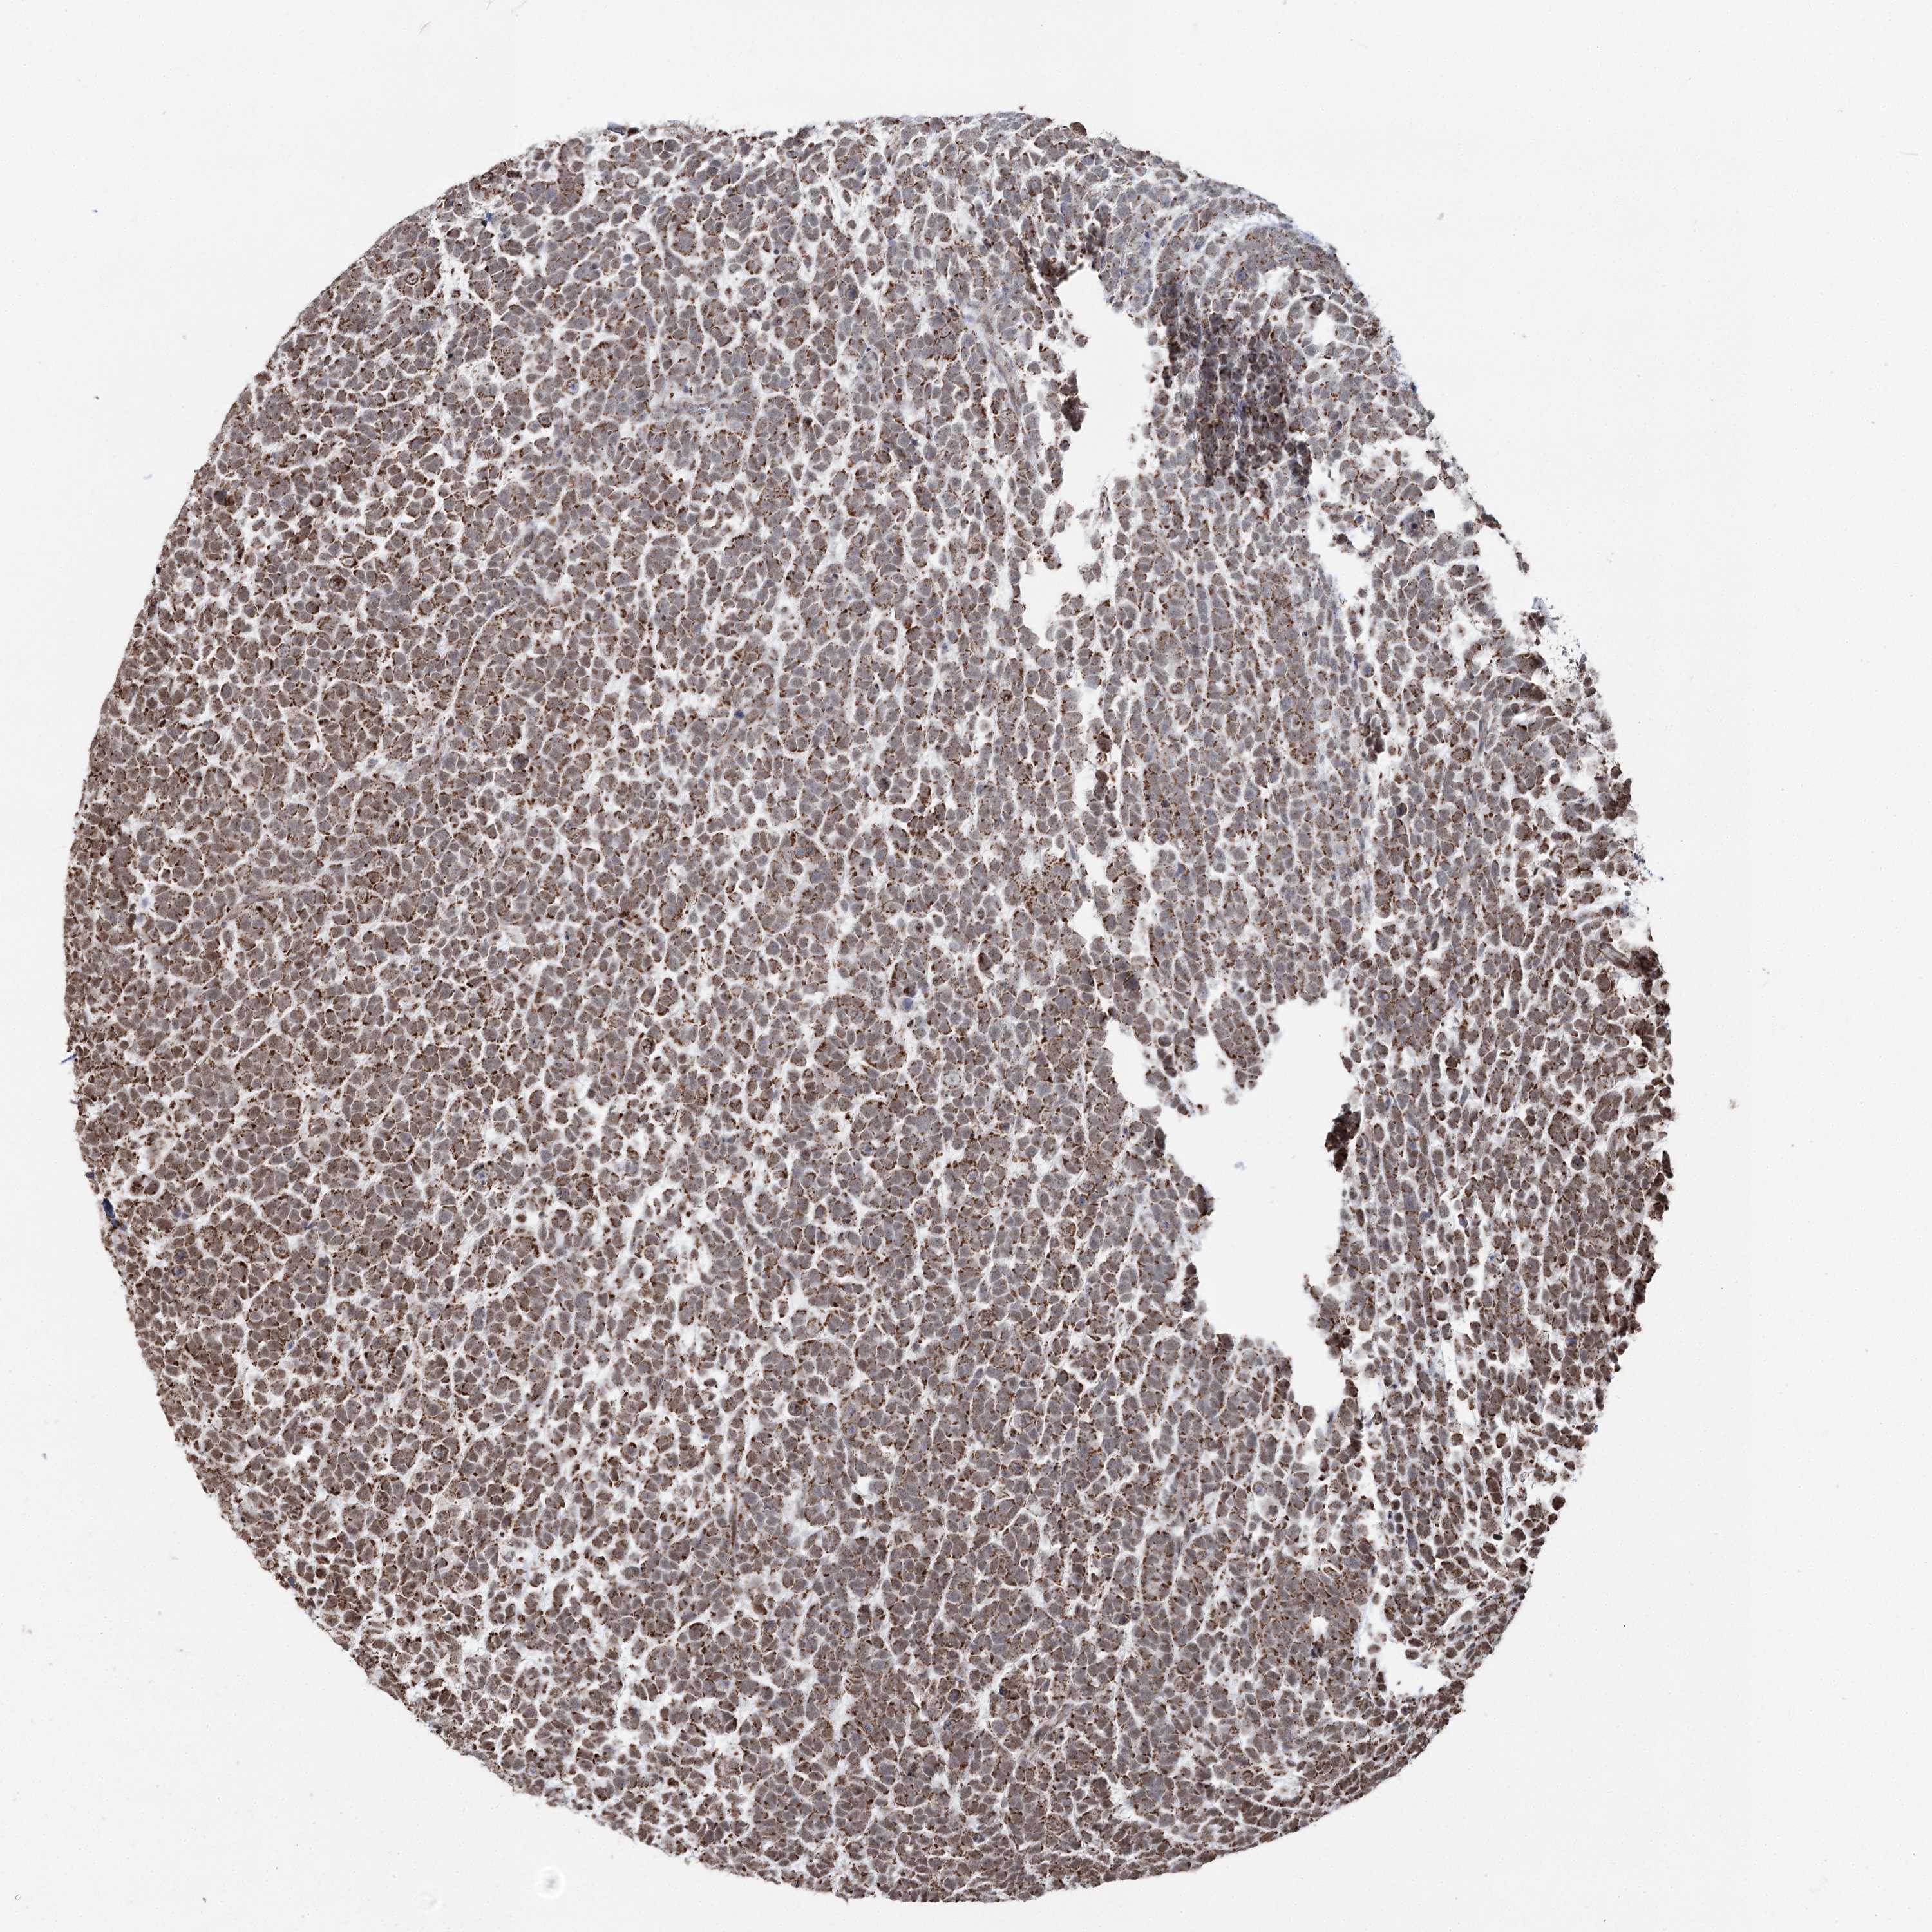

UROTHELIAL CANCER - Protein expressioni

A mouse-over function shows sample information and annotation data. Click on an image to view it in a full screen mode. Samples can be filtered based on level of antibody staining by selecting one or several of the following categories: high, medium, low and not detected. The assay and annotation is described here.

Antibody stainingi

Antibody staining in the annotated cell types in the current human tissue is reported as not detected, low, medium, or high, based on conventional immunohistochemistry profiling in selected tissues. This score is based on the combination of the staining intensity and fraction of stained cells.

Each image is clickable and will lead to virtual microscopy that enables deeper exploration of all samples and also displays staining intensity scores, fraction scores and subcellular localization as well as patient and tissue information for each sample.

Antibody HPA038484

Antibody HPA038485

Staining

High

Medium

Low

Not detected

Intensity

Strong

Moderate

Weak

Negative

Quantity

>75%

75%-25%

<25%

None

Location

Nuclear

Cytoplasmic/membranous

Cytoplasmic/membranous,nuclear

Urothelial carcinoma, High grade

Urothelial carcinoma, Low grade

Urothelial carcinoma, NOS